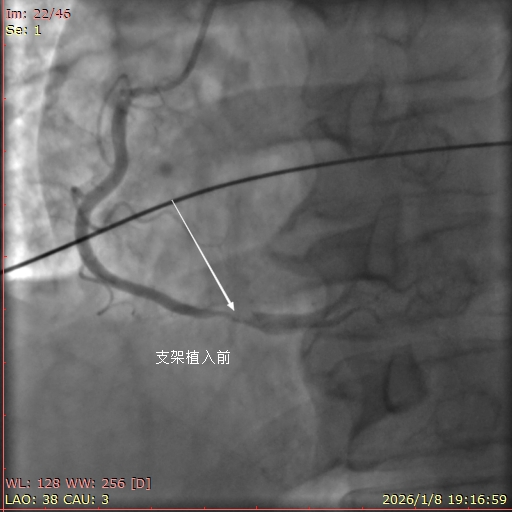

1月8日,17点40分患者潘某,男,51岁,江苏省人,因公来平度市新河化工园区出差,突发胸痛30分钟,就诊于当地胸痛救治单元,救治单元值班医师第一时间识别患者为高危胸痛,初步诊断为急性ST段抬高型心肌梗死,立即联系平度市第三人民医院胸痛中心,呼叫120,负荷量双联抗血小板聚集药物,吸氧,监护。急救中心接到呼叫后,立即出车。期间当地值班医师,患者的同事,领导都鼓励患者树立战胜疾病的信心!患者亲人未在身边,汇报给李丽院长助理,要求绿色通道,全力救治病人。院内导管室启动并激活。患者到达医院后绕行急诊和CCU直达导管室。冠脉造影提示右冠远段斑块破溃,99%狭窄,植入支架一枚,完全血运重建。胸痛救治单元与胸痛中心接力救治病人,无缝衔接,挽救了患者的生命,得到了患者及家人,同事,领导的赞许。(鲁网记者)